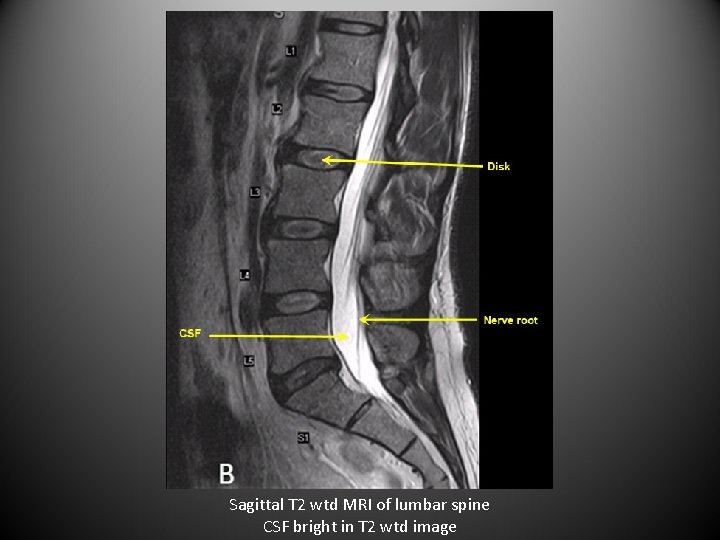

MRI Titbits • MRI can provide axial, sagittal and coronal views. • MRI is best for tissue discrimination and is superior to CT. • Look at pre-contrast and post-contrast MRI as a pair. • T 2 wtd MRI: There are many MRI sequences used to visualize specific tissues. • Flair and diffusion wtd images are a few examples. • The best way to distinguish T 1 wtd MRI from T 2 wtd MRI is by the appearance of CSF is bright in T 2 wtd MRI and CSF is dark in T 1 wtd MRI.

Sagittal T 2 wtd MRI of lumbar spine CSF bright in T 2 wtd image